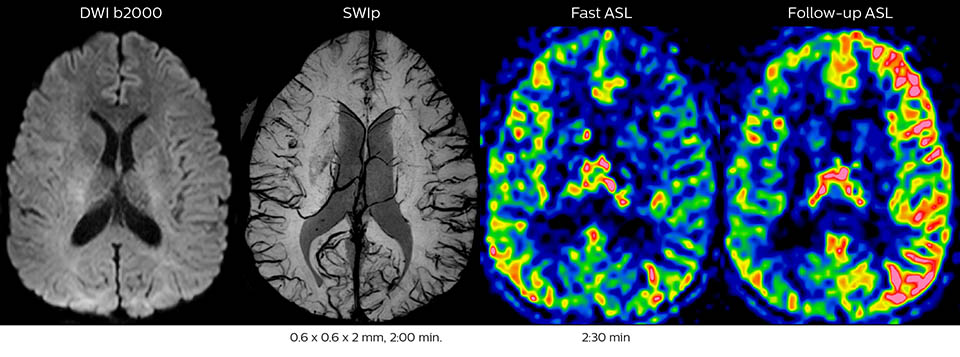

Acute right motor deficit and aphasia

In this patient with acute right motor deficit and aphasia, the b2000 diffusion weighted image is normal. The SWIp image demonstrates more prominent veins in the right hemisphere, which could reflect increased deoxyhemoglobin contents. Fast ASL shows low CBF regions in the left frontal lobe. A follow-up ASL after one hour demonstrates high CBF values in the same area. The final diagnosis was migraine with aura.